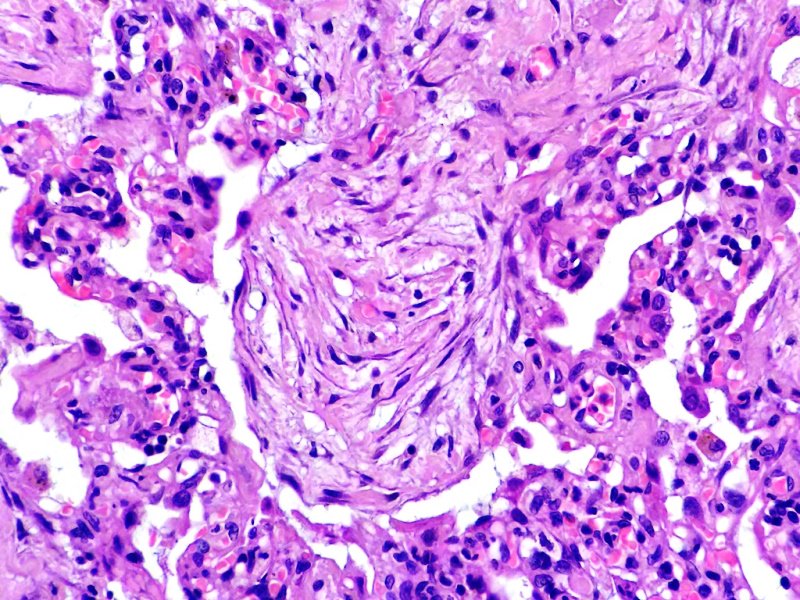

Epidídimo. Cistadenoma papilar. Tinción HE